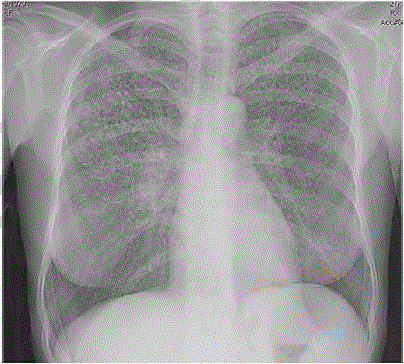

Uma paciente de 45 anos de idade compareceu, acompanhada pela filha, a consulta ambulatorial. Queixa-se de perda de peso (em tomo de 4 kg nos últimos seis meses), febre vespertina e fadiga há mais de 20 dias. Observou que tem trabalhado muito, tem uma fadiga crônica e acha que iniciou os sintomas após exposição à chuva e a vento frio quando voltava do trabalho para casa. Ela informa que é etilista social e tabagista (15 cigarros/dia), e apresentou alguns exames laboratoriais como hemograma, eletrólitos, função hepática e renal normais. Os raios X de tórax estão representados na imagem a seguir. O resultado do PPD e o lavado brônquico são negativos.

Com base nesse caso clínico, na imagem apresentada e nos conhecimentos médicos correlatos, julgue os itens a seguir.

A imagem dos raios X de tórax coloca a tuberculose como diagnóstico diferencial.